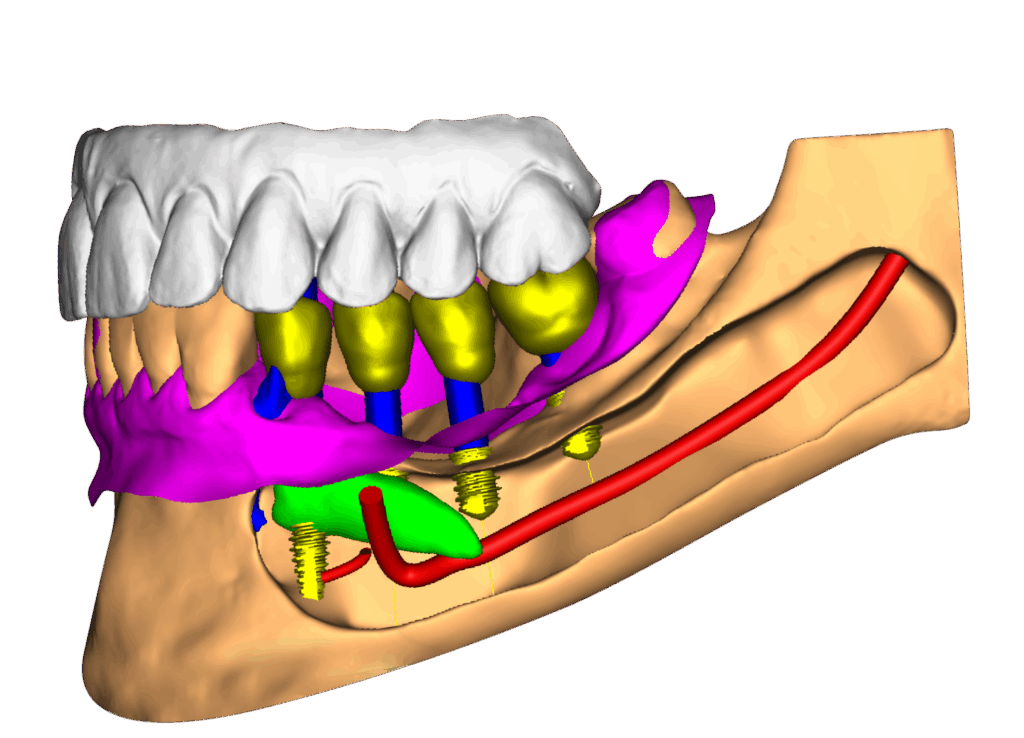

É o procedimento da realização de implante(s) de maneira guiada, com total segurança, uma cirurgia com possibilidade de não haver cortes, reduzido sangramento e pós-operatório rápido e na grande maioria das vezes totalmente indolor. Para obter o guia é necessário fazer tomografia e escaneamento da arcada dentária. Com esses exames e um software de planejamento será feito o planejamento em 3D dos implantes e gerado uma guia de implantes, a qual será posicionado em boca para direcionar a correta perfuração e instalação dos implantes. A precisão do posicionamento dos implantes com o uso do guia, permite, além dos benefícios cirúrgicos, que o(s) dente(s) da prótese já possam ser confeccionados previamente, e já estarem prontos para serem instalados no dia da cirurgia.